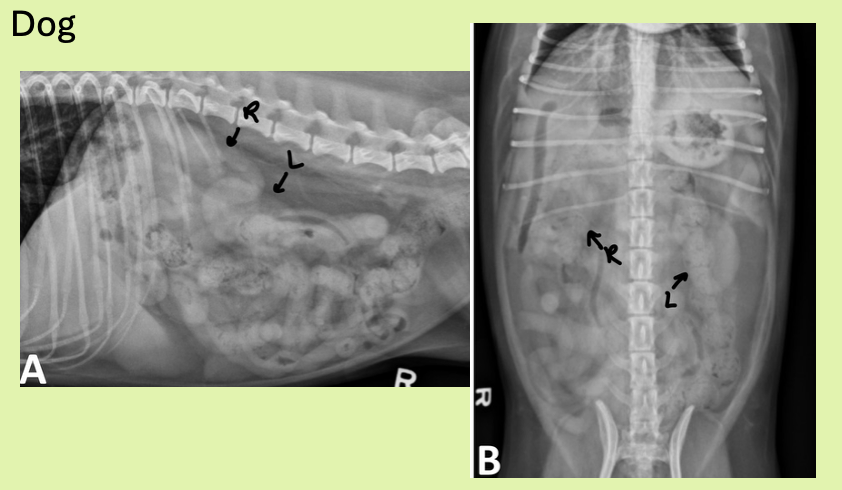

which view is best for eval of SIZE and shape of kidneys

VD

where are right and left kidney located

R kidney - 13th rib where cr. pole touches caudate lobe of liver

L kidney - more cd. than right kidney. Just behind gastric fundus, cd/med to splenic head

how are cat kidneys located differently from dog

more cd (same thing with right kidney more cr.)

dog kidney size vs cat kidney size

dog - 2.5-3.5 x length L2

cat - 1.9-3.2 x length L2

shape of kidneys dog vs cat

dog - bean

cat - oval